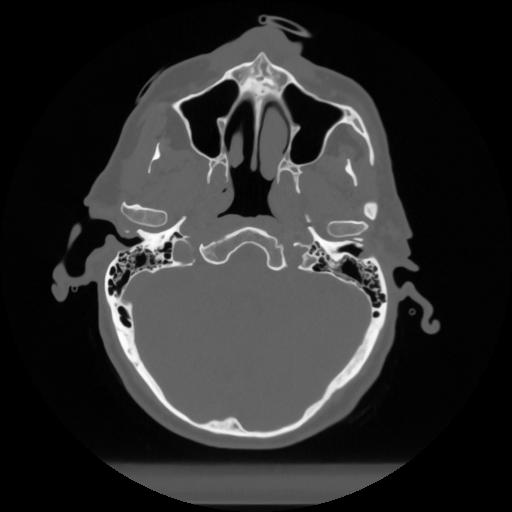

12 P.BLANDAS,,Vol,0.5,P.BLANDAS,,